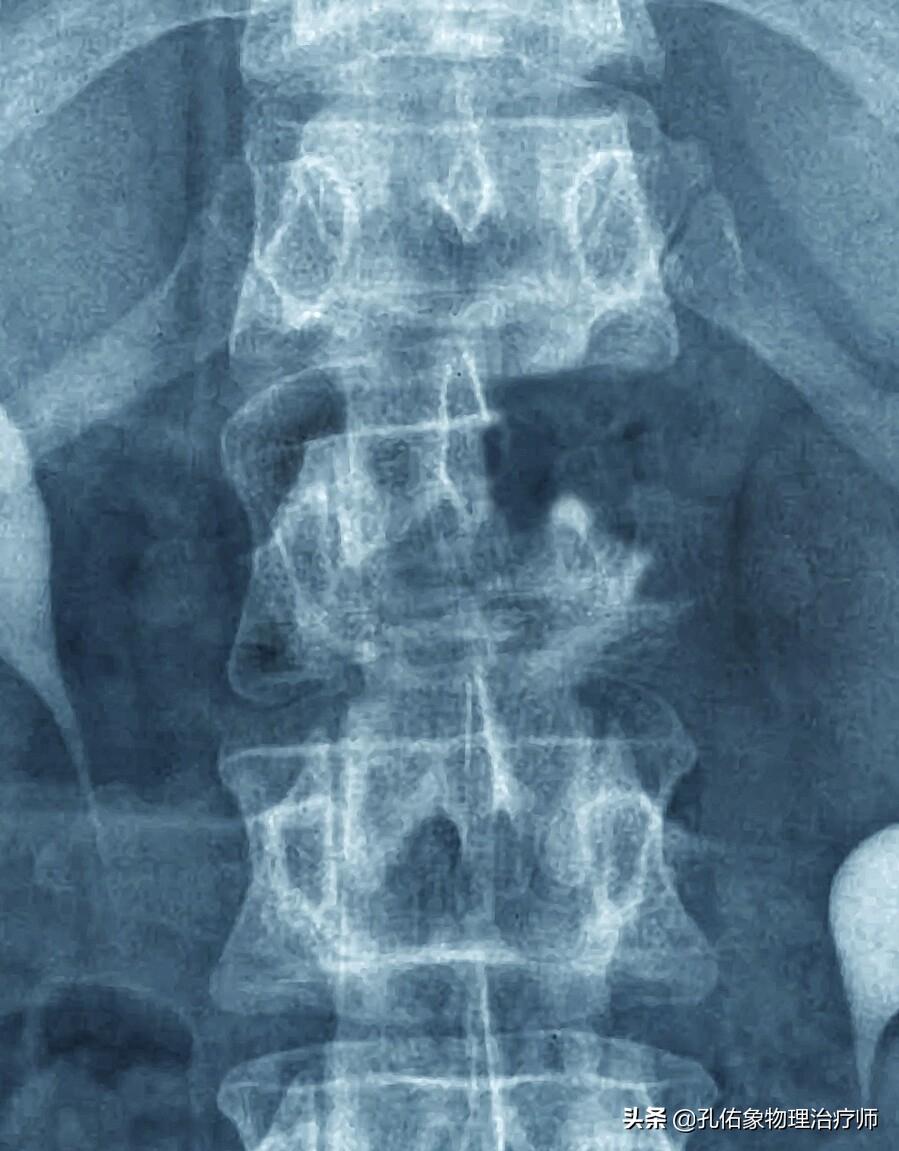

3.案例三:一位亲戚是某氮肥厂的职工,因为长年累月的弯腰,经常会腰疼,去过好多地方看,都告诉他是慢性腰肌劳损,伴随着疼痛多年;突然有一天腰痛加重,疼痛剧烈,才来到省城医院就诊,最终查出是腰椎恶性肿瘤,肺癌的骨转移,没多久就不在人世了。